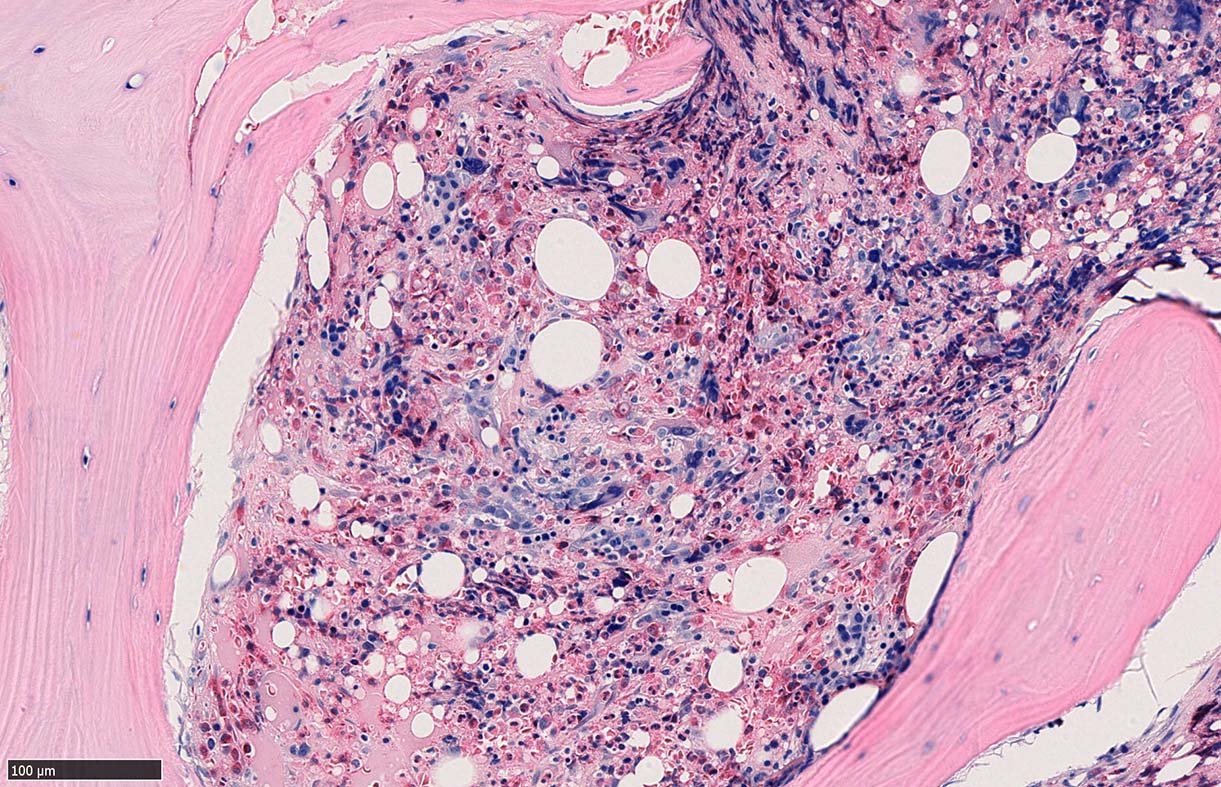

骨髄組織所見 bone marrow biopsy total 6mm in length

塗銀染色